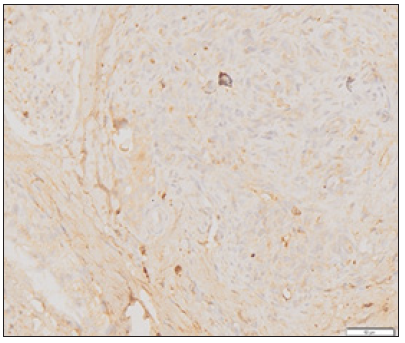

Assessment was given in the form of ordinal scale scores with a total score ranging from 2-16. Figure 1-3 shows a picture of the myoblast cell anatomical pathology binded to the reagent myoD1 at various intensities. Research results for the three groups of rabbits were descriptively shown in the Figure 4. Figure 4 illustrates the scoring of myoblast from muscle healing in rabbits. Based on these data it can be seen that the lowest score in the dextrose group is 8, the highest score is 16 and the mean score is 10.1; lowest score at control group is 2, the highest score is 12 and the mean score is 6.4; Indicating that 10% dextrose group mean score was higher than control group. Then the Mann Whitney test was done to see whether there is significant difference in the number of myoblasts cells in the rabbit’s muscles between the dextrose group and the control group. Based on the statistical calculation, it was obtained that Z value -2,432 with P value 0.015. This statistical analysis showed that the value of P<0.05. Therefore, we can conclude that there are differences in the number of myoblast cells in the rabbit’s muscles in the 10% dextrose group towards the control group.

Figure 1: Picture of myoblast cells that bind MyoD1 on strong intensity.

Figure 2: Picture of myoblast cells that bind MyoD1 at moderate intensity.

Figure 3: Picture of myoblast cells that bind MyoD1 on weak intensity.